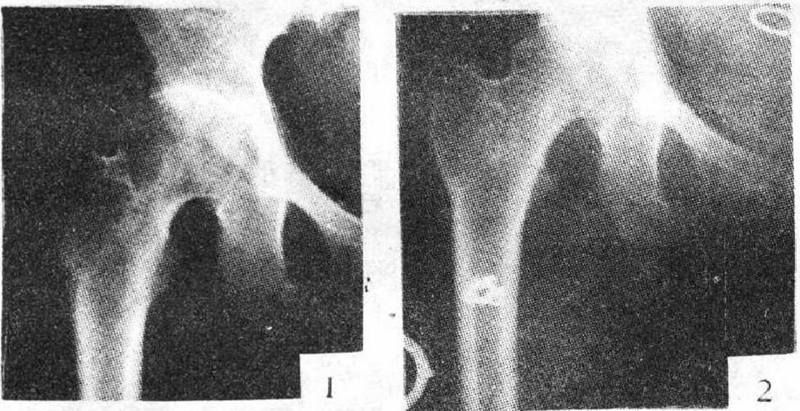

1、传统单孔(Single CD,SCD)髓芯减压术

单孔髓芯减压术是使用8~10mm的环钻或空心针,在X线透视下从转子下方骨皮质经股骨颈达到股骨头坏死区域,进而清除坏死骨组织,其临床疗效常取决于分期。

2、细孔径双通道钻孔髓芯减压术

1987年起,浙江省中医院团队设计粗隆下5mm孔径、双通道、股骨头倒V形钻孔加丹参灌注,治疗成人股骨头坏死54例,经过2~8.5年临床观察显示,该方法疗效明显,总优良率达81%,Ⅰ~Ⅱ期优良率达94%。